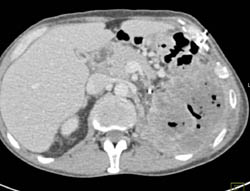

Lack of Gastric Distention Limits Study